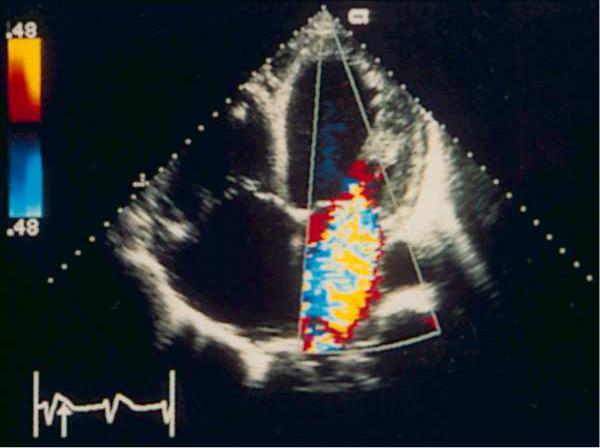

Fig.3 The position of the apical four-chamber hearts. Color Doppler study systolic. Severe mitral insufficiency. The jet has a large diameter at the level of the cusps of the mitral valve, the flow reaches the opposite wall of the left atrium occupies almost all the left atrium and enters the pulmonary veins — these trait s characterize severe mitral regurgitation.